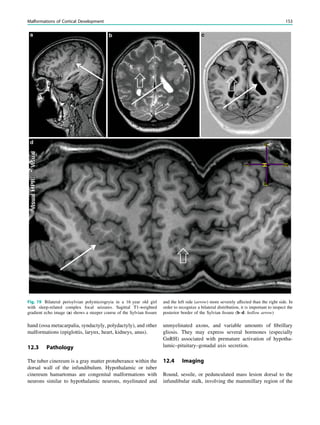

Fig. 2 Dural a. v. fistula. A 53-year-old man presented with two tonic–

clonic seizures. MRI shows circumscribed edema in the left frontal lobe

(a, hollow arrow) and an abnormal vessel running in the left sulcus

rectus (c, arrow). The digital subtraction angiogram of the left internal

carotid artery shows a frontobasal dural arteriovenous fistula fed via

ethmoidal arteries (d, arrow) and confirms the abnormal vessel as a

draining vein (e, arrow)